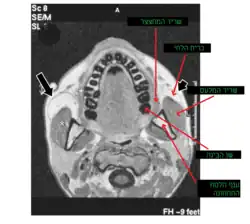

Nas proximidades de seu centro, com algumas variações, encontra-se o forame da mandíbula, cuja margem anterior é coberta pela língula da mandíbula; esse forame é limitado, abaixo, pelo sulco milo-hióideo e constitui a porta de entrada do extenso canal da mandíbula, percorrido pelo feixe vasculo-nervoso destinado à irrigação e inervação dos dentes inferiores.

A mandíbula é composta por duas camadas de osso compacto: uma lateral e uma medial. Entre essas camadas há uma quantidade variável de tecido esponjoso, segundo a região que se considere: escasso no processo coronóide e abundante na cabeça da mandíbula, que é coberta por uma delgada lâmina de tecido compacto.